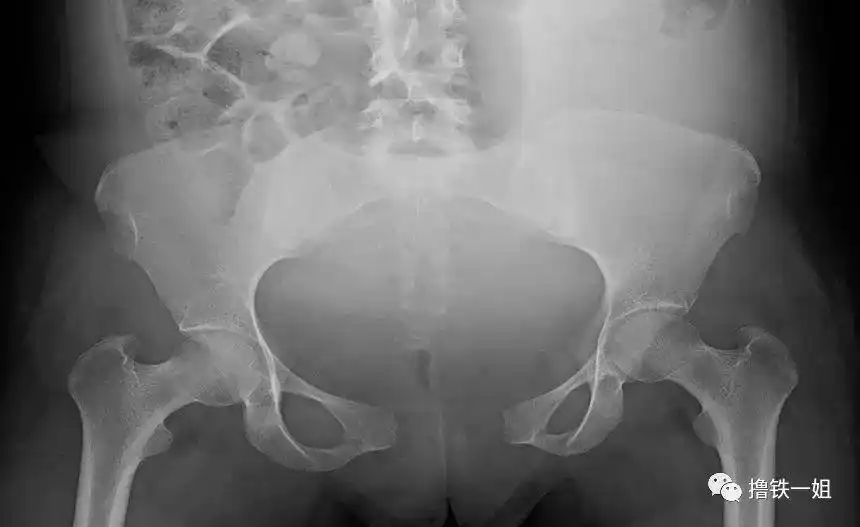

盆腔dr正位片示膀胱结石.

原创在x光片上如何辨别骨盆前倾与后倾